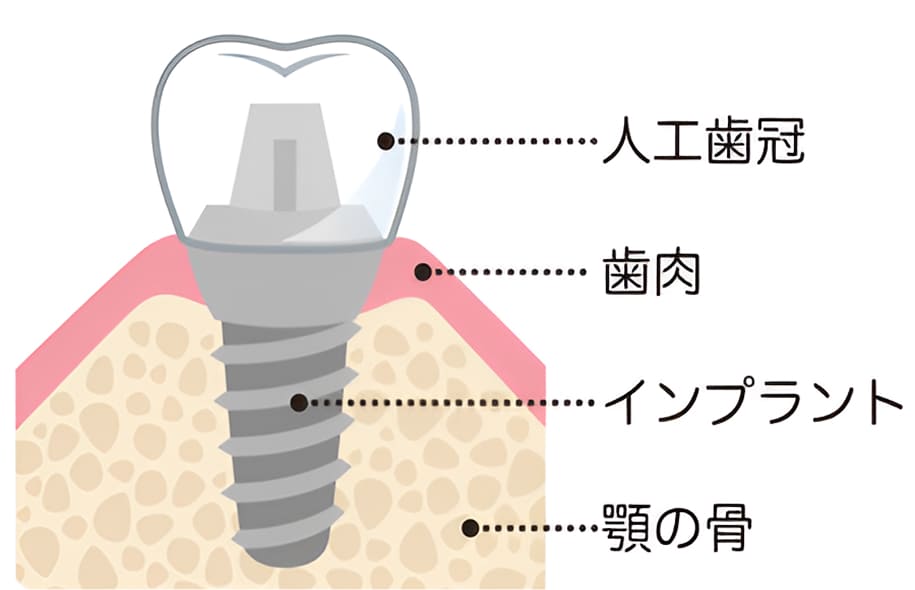

人工歯根療法とも言われ、歯を支える顎骨部分にボルトを埋め込み、人工の歯を被せる治療方法です。メリットとしては、ご自身の歯と同じような感覚で噛めるようになることが挙げられます。審美性が高いため、美しく仕上がることもインプラントの特長です。留意点としては、治療期間が長く、保険適用外のため治療費は高額になります。

インプラント治療とは

歯を失ってしまった部分の顎の骨にチタン製の人工歯根(=インプラント)を埋め込み、その上部に人工の歯冠を装着して歯の機能と見た目を同時に補う治療法です。

人工歯根に用いられるチタンには顎の骨としっかり結合する性質があり、1本で独立して固定されるので、本物の歯のような咬み心地を再現できます。